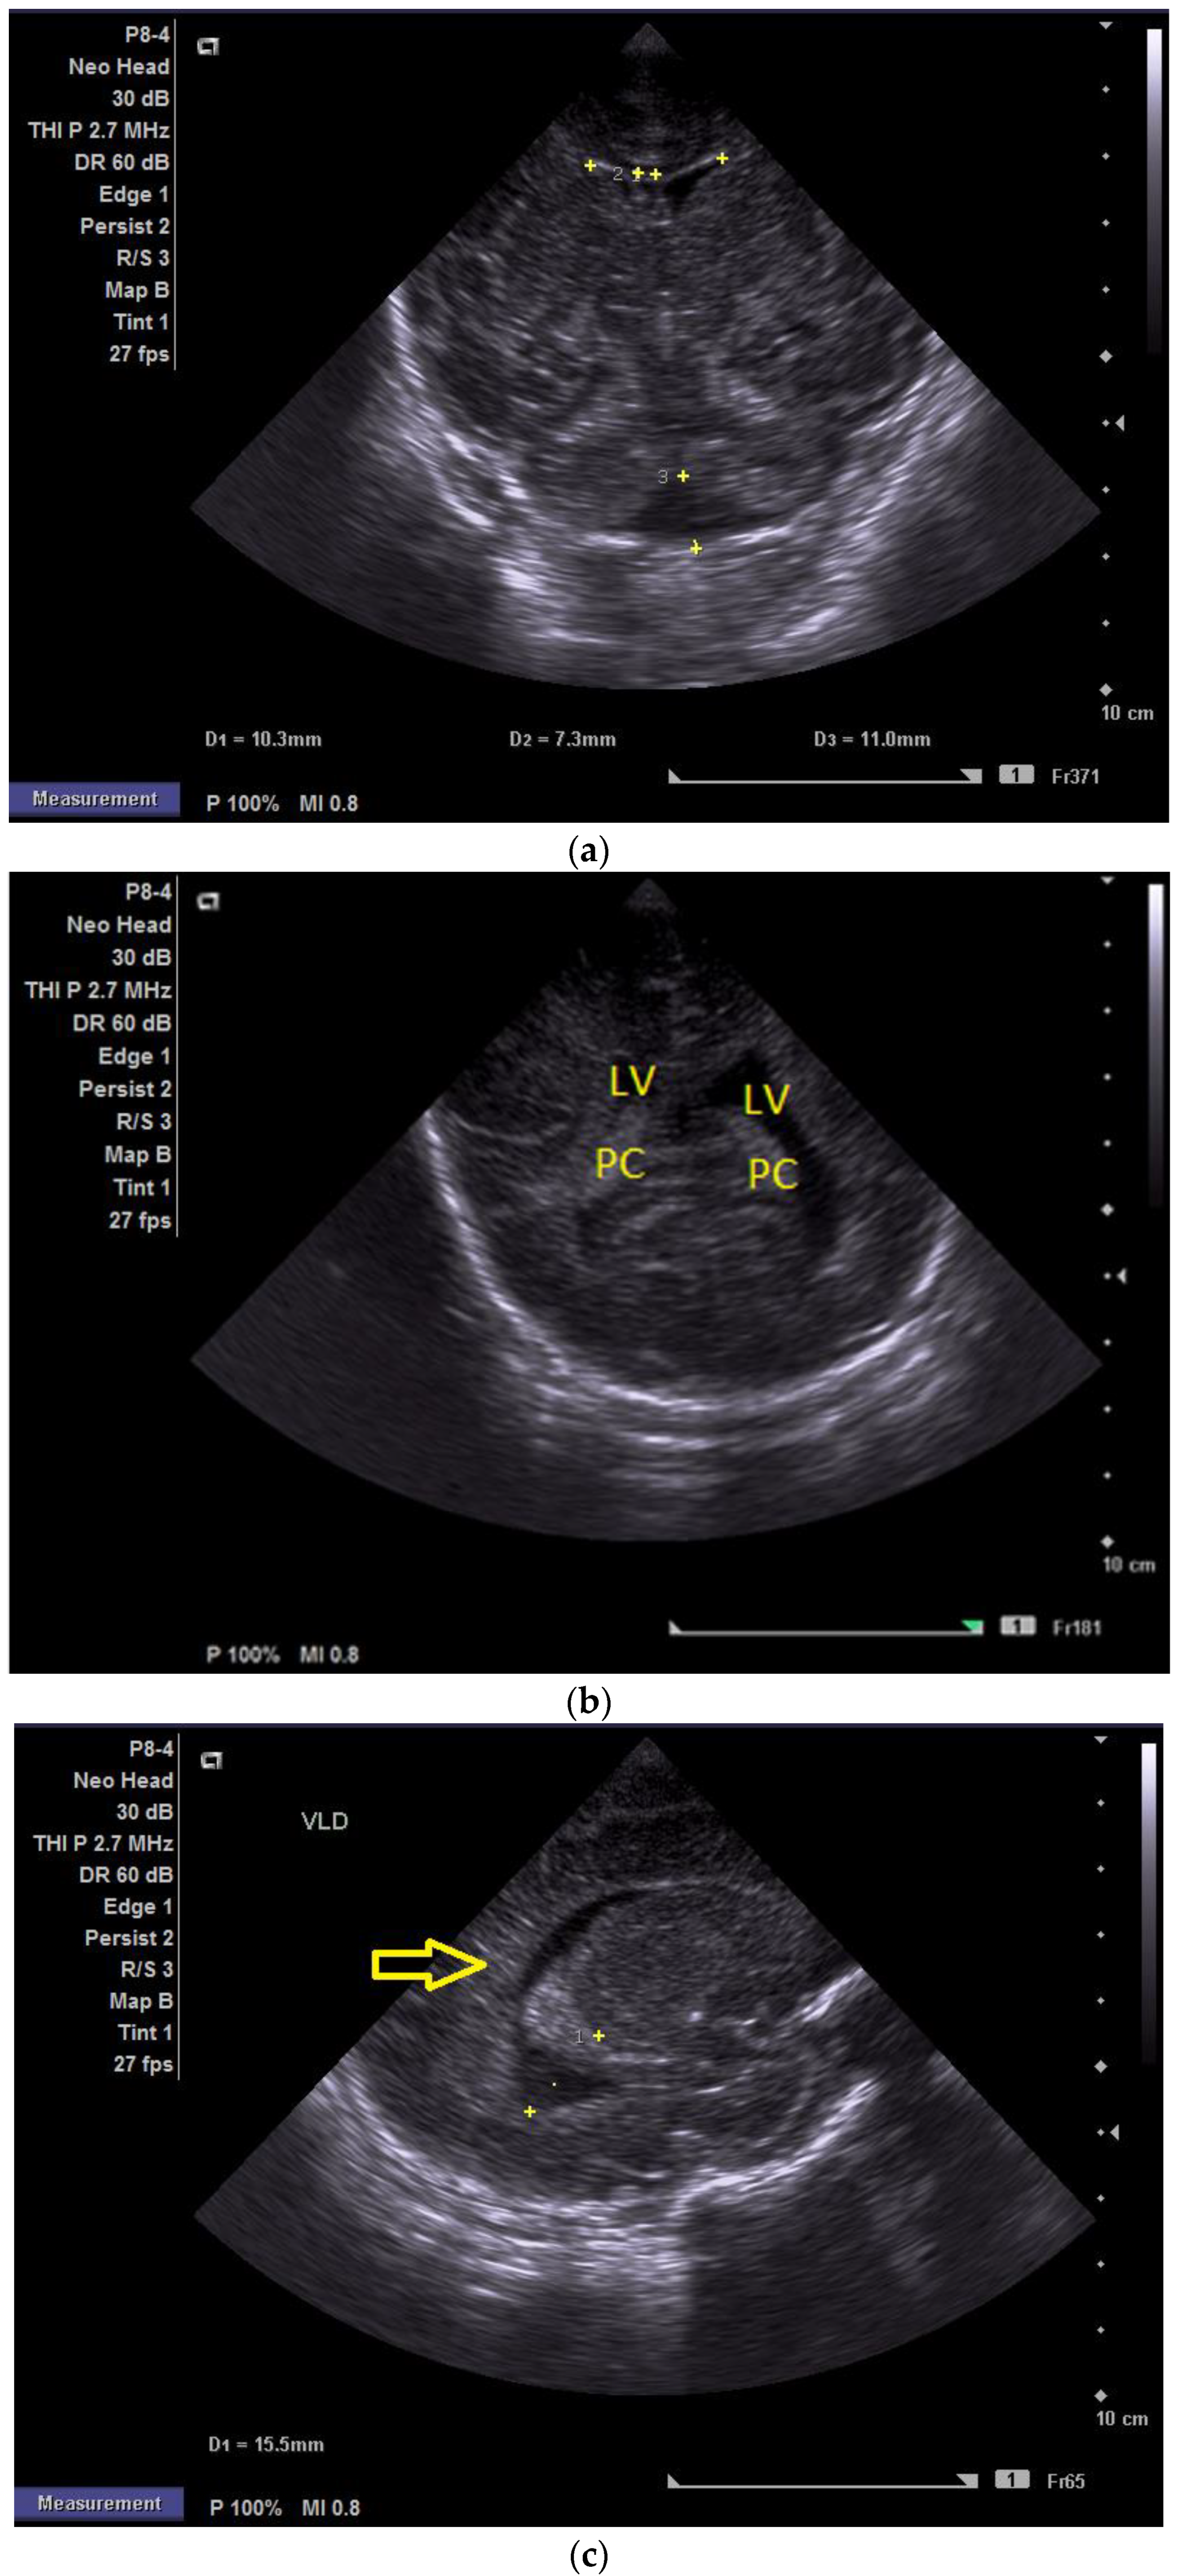

At two minutes of life, with a heart rate of 120 bpm, chest compressions were discontinued, and the patient continued to be ventilated via endotracheal tube. The newborn was then transported while ventilated in an incubator to the neonatal intensive care unit (NICU), where SIMV ventilation was initiated, along with surfactant administration. The day one cranial ultrasound (CUS) showed bilateral periventricular hyperechoic images and enlargement of the lateral ventricles (Figure 1a–d).

Figure 1.

(a) Cranial ultrasound. Day one. Coronal view. D1 and D2—Levine index measurement. D3—cisterna magna measurement (personal image collection). (b) Cranial ultrasound. Day one. Coronal view. Lateral ventricle dilatation. LV—lateral ventricles. PC—plexus choroidus (personal image collection). (c) Cranial ultrasound. Day one. Right lateral ventricle. D1—thalamo-occipital distance measurement. Yellow arrow—parieto-occipital hyperechoic images (personal image collection). (d) Cranial ultrasound. Day one. Left lateral ventricle. D1—thalamo-occipital distance measurement. Yellow arrow—parieto-occipital hyperechoic images (personal image collection). (e) Day three. Cranial ultrasound. Coronal view. Ventricular asymmetry. D1 and D2—Levine index measurement. D3 and D4—anterior horn width measurement. Left ventricular enlargement (personal image collection). (f) Day three. Cranial ultrasound. Coronal view. Ventricular asymmetry (left ventricle larger than right ventricle). Yellow arrows—periventricular hyperechoic images are becoming more visible (personal image collection). (g) Day three. Cranial ultrasound. Coronal view. Linear probe. Ventricular asymmetry (left ventricle larger than right ventricle). LV—lateral ventricle (anterior horns). IHF—interhemispheric fissure. Yellow arrows—hyperechoic images in the thalamic-caudate groove (suggestive of a germinal matrix hemorrhage) (personal image collection). (h,i) Day 13. First LP. Cranial ultrasound. Coronal view. Up (before LP). D1 and D2—Levine index measurement. LV—lateral ventricles (anterior horns). IHF—interhemispheric fissure. Down (after LP). Dimensions of ventricles were reduced after LP. D1 and D2—anterior horn width. LV—lateral ventricles (anterior horns). OH—occipital horn (personal image collection). (j,k) Day 19. Second LP. Cranial ultrasound. Coronal view. Dimensions of ventricles were reduced after LP. Left (before LP). D1 and D2—Levine index measurement. Right (after LP). D1 and D2—Levine index measurement (personal image collection). (l) Day 39. Cranial ultrasound. Coronal view. Yellow arrows—periventricular cystic hyperechoic images—suggesting periventricular leukomalacia (cystic form) (personal image collection). (m) Head circumference-for-age. “X” symbols represent the measurements performed from birth and follow-up examinations. Initially, the head circumference was under the curve (personal image collection) [28].

After 72 h, the patient was extubated. The CUS showed bilateral IVH (grade III Volpe/Papile) (Figure 1e,f).

During the in-stay, two lumbar punctures (LP) were performed (Figure 1h–k).

In evolution, our patient presented bilateral ventricular dilatation and bilateral PVL (cystic form, grade III) (Figure 1l). The neurological assessment established eye contact and the infant could hold its head during the traction maneuver. The passive tone assessment showed the “scarf sign”, with the elbow at the midline bilaterally and a popliteal angle of 90°. The deep tendon reflexes (DTRs) were symmetrical.